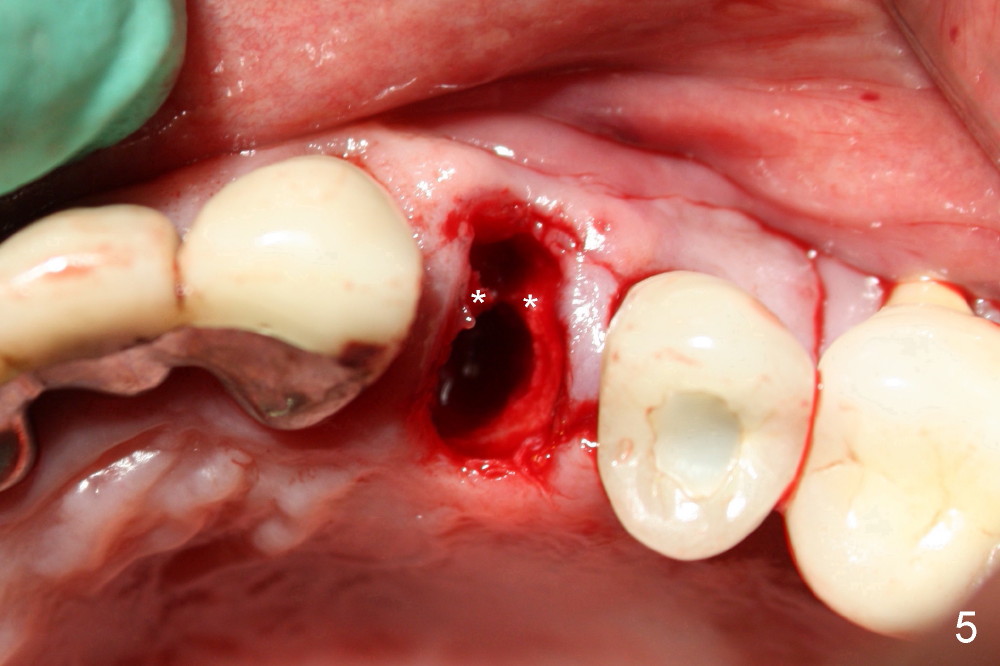

A 50-year-old man has mild pain in the upper left 1st bicuspid 3 years after root canal retreatment with placement of two posts (Fig.1). Findings of clinical exam are consistent with root fracture (Fig.2). Extraction reveals two fused roots (Fig.3,4). Probing indicates that the buccal plate is defective. Osteotomy is initiated in the palatal socket with a 2 mm pilot drill, followed by 2.5 and 3.0 mm reamers and 4.5x20 mm tap. The septum appears to have been pushed buccally (Fig.5 *) and form a new buccal wall (partially, strengthened by bone graft mentioned below) for the implant to be placed. The implant (4.5x20 mm) is placed in the palatal socket (Fig.6 *) with insertion of an abutment (A: 3.5x5 mm 0º), while a mixture of autogenous bone (harvested from reamers) and Synthograft (Bicon) is placed in the shrunken buccal socket (Fig.7; using allograft may decrease postop bony shrinkage). The bone graft is then contained by an immediate provisonal without collagen membrane or flaps. The patient is doing well postop. The gingiva is healthy (Fig.8*) when the provisional is removed 3 months postop with normal papillae (Fig.9 arrowheads). It remains the same 1 month post cementation (Fig.10,11). For further follow up, see immediate implant of the tooth #13.